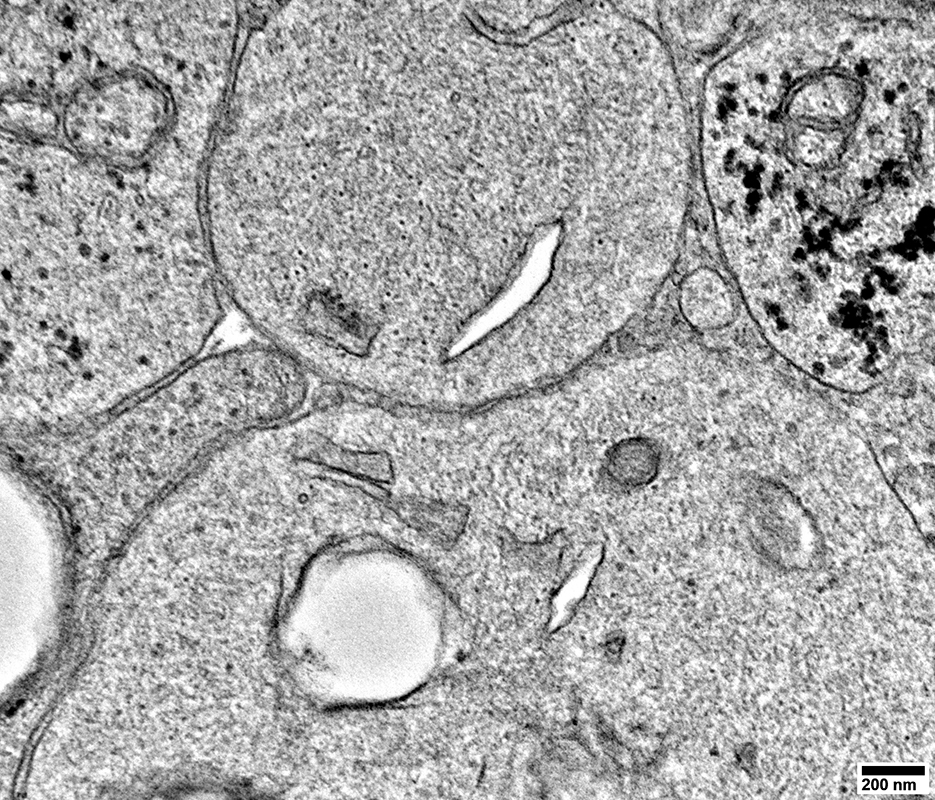

Lipid Droplets & Myelin debris segregated in different Schwann cell processes

Axons surronded by thin Schwann cell processes containing Myelin, or Lipid, Debris

Axons surronded by multiple small Schwann cell processes